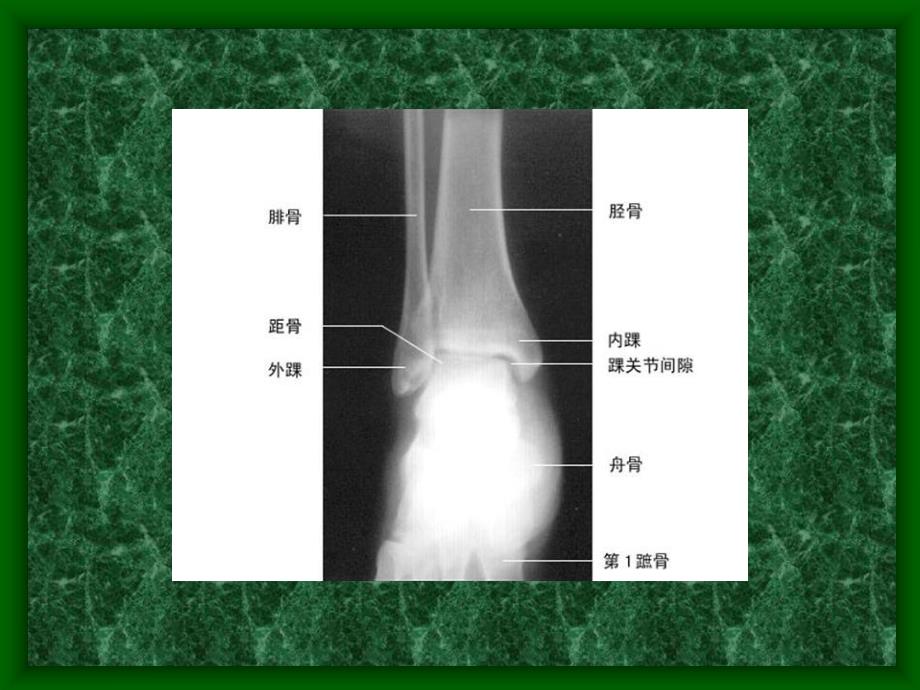

1、关节松动术踝关节部分踝关节 构成构成:下胫腓关节、胫距(距上)关节、距下关节、跗骨间关节 生理运动生理运动:跖屈、背伸、内翻、外翻。附属运动附属运动:长轴牵引、前后向、后前向、上下滑动 踝关节a)胫腓前韧带和胫骨前结节Tillaux-Chaputb)胫腓后韧带踝关节a)外侧韧带复合体1.跟腓韧带2.前后距腓韧带3.前后胫腓下联合b)内侧韧带复合体或三角韧带踝关节主要松动技术跖屈、背屈内翻、外翻内旋、外旋踝关节后前运动踝关节前后运动向尾部的纵向运动向头部的纵向运动下胫腓关节前后运动下胫腓关节后前运动下胫腓关节挤压距下关节后前运动上腓骨小头的松动参考下胫腓关节下胫腓关节 前后向或后前向滑动前后向或

2、后前向滑动增加踝关节活动范围。胫距关节胫距关节 分离牵引分离牵引一般松动,缓解疼痛。前后向滑动前后向滑动增加踝背伸活动范围。参考后前向滑动后前向滑动增加踝跖屈活动范围。向内侧滑动向内侧滑动增加踝外翻活动范围。外内侧滑动外内侧滑动增加踝内翻活动范围。伸屈摆动伸屈摆动增加踝屈伸活动范围。翻转摆动翻转摆动内翻摆动:增加内翻活动范围;外翻摆动:增加外翻活动范围。参考距下关节距下关节 分离牵引分离牵引一般松动,缓解疼痛。前后向滑动前后向滑动增加背伸活动范围。后前向滑动后前向滑动增加跖屈活动范围。侧方滑动,屈伸摆动及屈翻转摆动。同胫距关节的手法。参考跗骨间关节跗骨间关节与腕骨一样 上下滑动上下滑动增加踝背屈及跖屈活动范围。跗跖关节跗跖关节 上下滑动上下滑动增加跗跖间活动。旋前摆动旋前摆动增加外翻活动范围;旋后摆动旋后摆动增加内翻活动范围。踝关节踝关节背屈踝关节背屈踝关节后前运动距下关节后前运动距下关节距下关节后前运动距下关节后前运动距下关节后前运动距下关节后前运动距下关节后前运动踝关节后前运动踝关节向头部的纵向运动踝关节向尾部的纵向运动踝关节向尾部的纵向运动踝关节内翻/外翻下胫腓关节前后运动下胫腓关节前后运动下胫腓关节挤压腓骨小头的松动